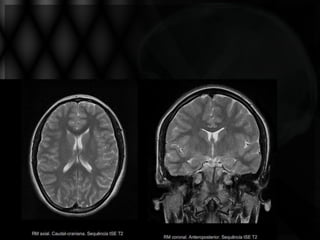

NEUROANATOMIA E ORGANOGÊNESE

GIROS E SULCOS

Central

Sylvius

Parietoocciptal

Reconstrução 3D por RMN

VISÃO CORONAL

DIMINUIÇÃO VOLUMÉTRICA

GIROS FACE SUPEROLATERAL

FACE MEDIAL- GIROS E SULCOS

CÚNEO

OCCIPTOTEMPORAL MEDIAL

GIROS- VISÃO MEDIAL